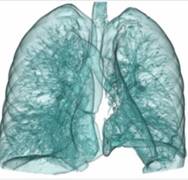

儿童呼吸运动及肺功能研究

肺小占位性病变和弥漫性病变的鉴别诊断分析

肺气管、支气管随呼吸运动气道变化

泌尿系成像 肺动脉栓塞 肺透明成像